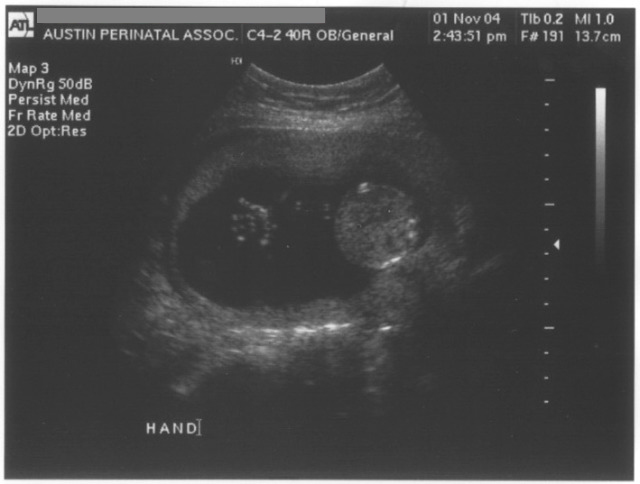

11/1/04